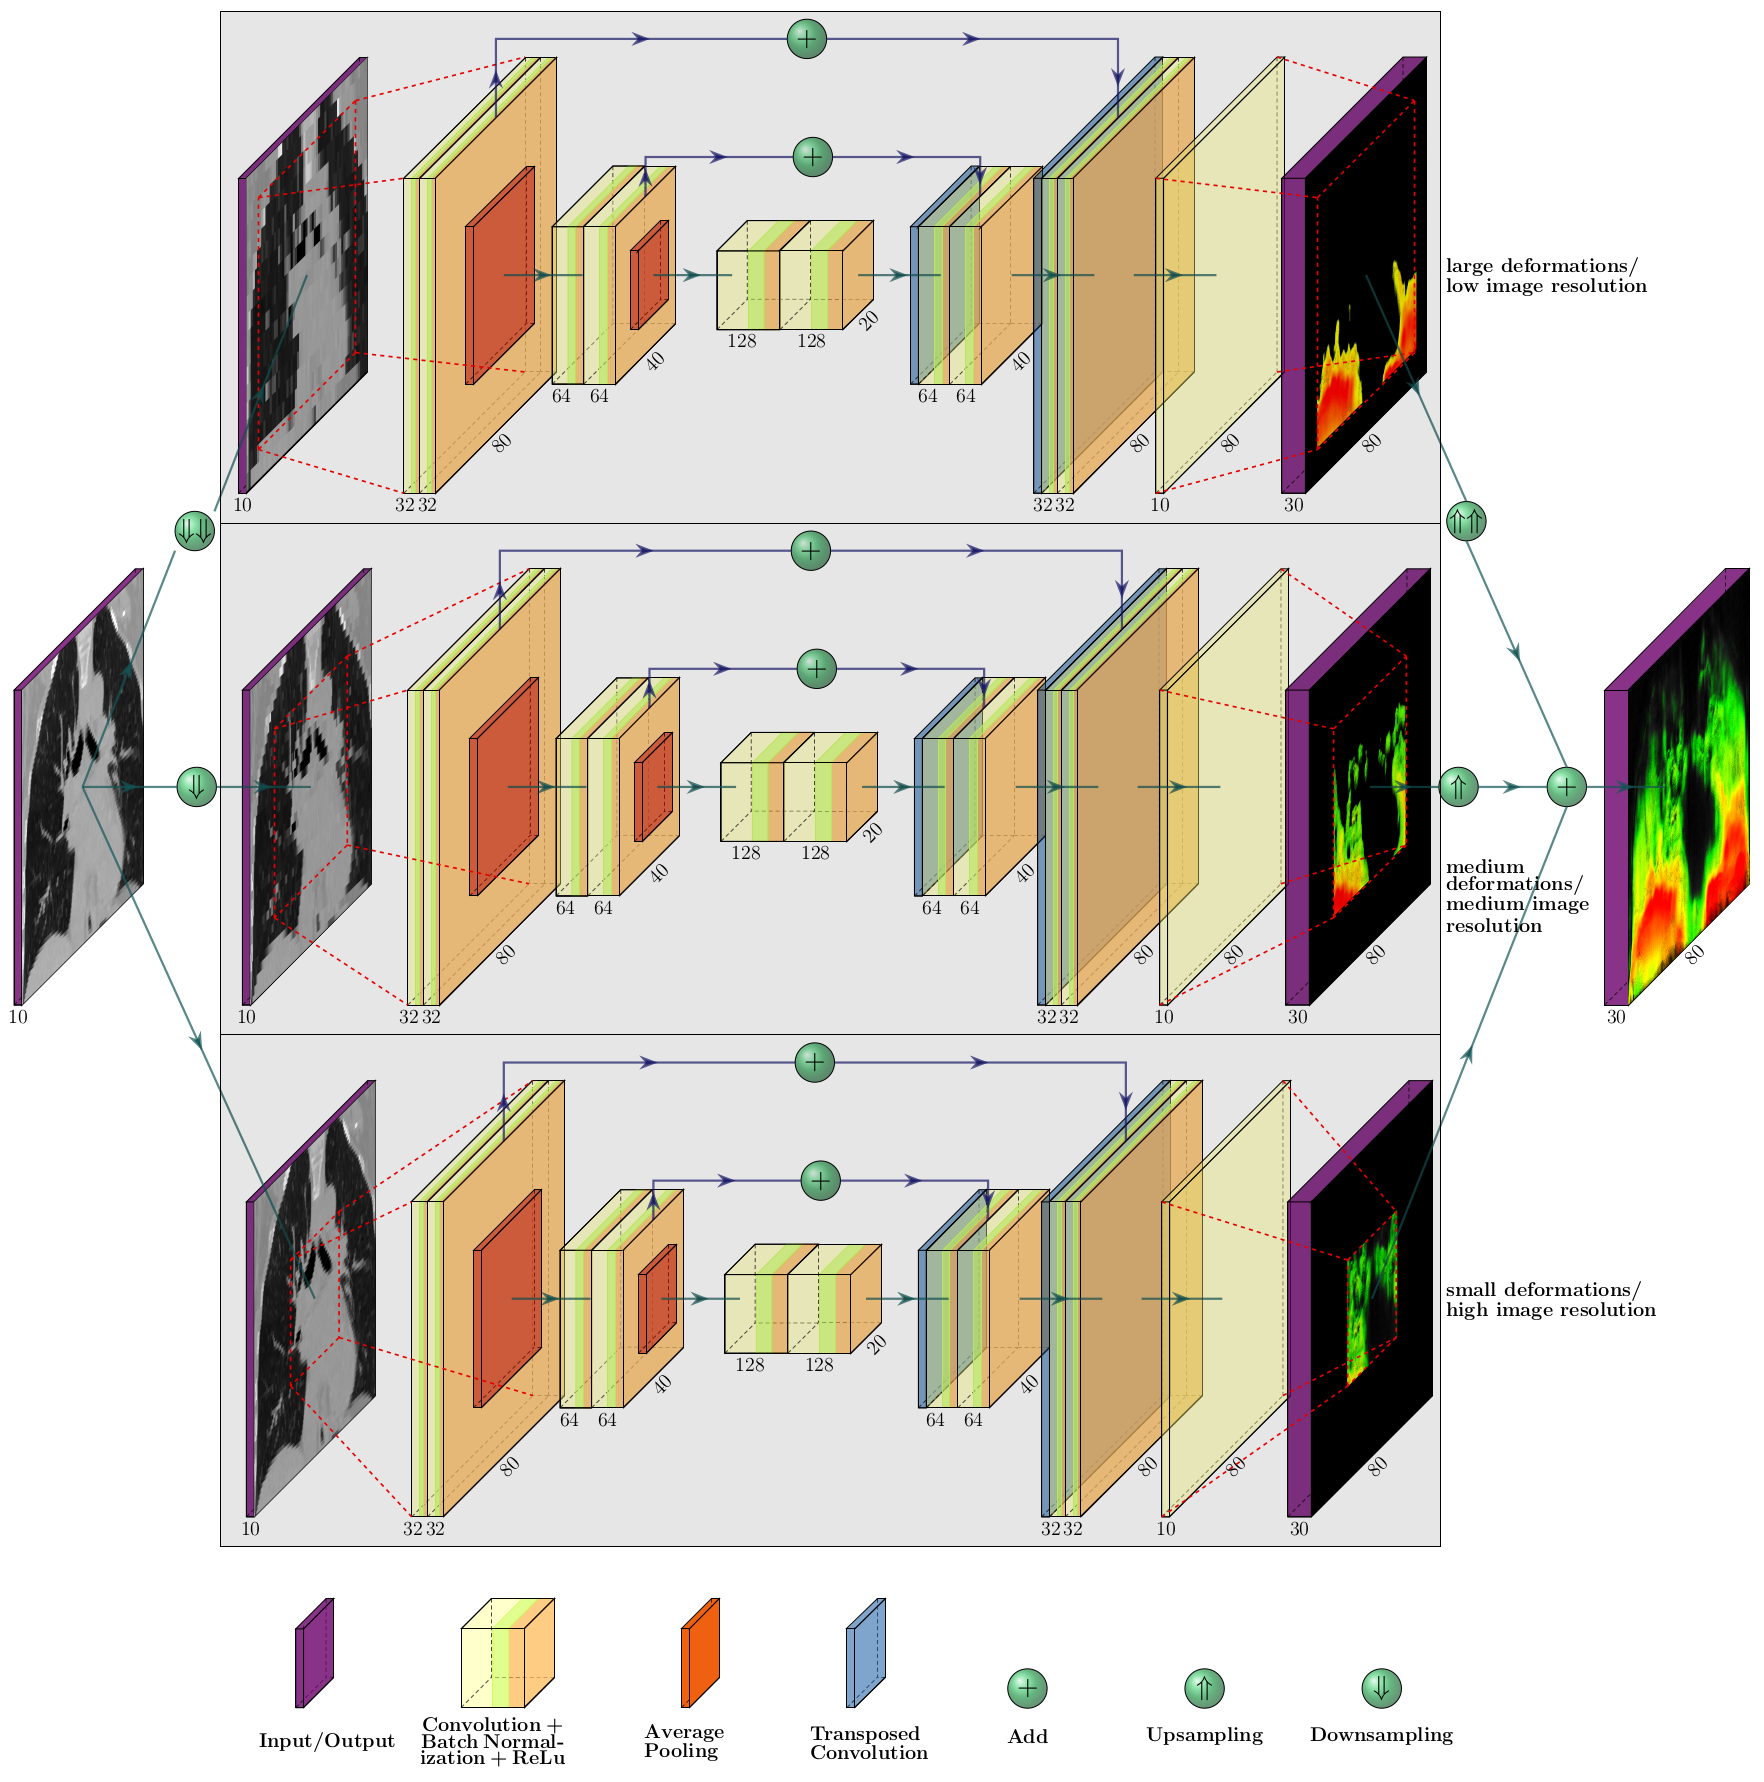

Following the recently published works about DL based image registration [18, 13, 14, 15, 16, 17] we decided for a CNN based architecture. Similar to [18] we employed the U-net architecture [34] with 2 downsampling steps with average pooling layers, 2 upsampling steps with transposed convolution layers [35] and skip connections by summation instead of concatenation. The network takes or a patch of as input (each phase image as a single channel) and calculates deformation fields with the network parameters . An illustration of all layers and connections can be found in Fig. 1.

The combination of patch based processing and the receptive field of voxels limits the ability of the presented network to account for large deformations (occurring e.g. in the diaphragmatic region). Thus we adopted a coarse-to-fine approach like it is often used in conventional image registration [36]. Our multi-resolution approach consists of 3 image registration steps. First, basic deformations are calculated with the input image downsampled by a factor of 4. This step is repeated with the input image downsampled by a factor of 2 to capture intermediate deformations. In a last step the original image is fed to the network. The calculated vector fields of a respective downsampling step are added to the upsampled vector fields of previous steps before the loss is calculated. Thereby, the net first calculates a basic deformation field and adds more and more details after every upsampling step. The whole multi-resolution architecture is depicted in Fig. 1.